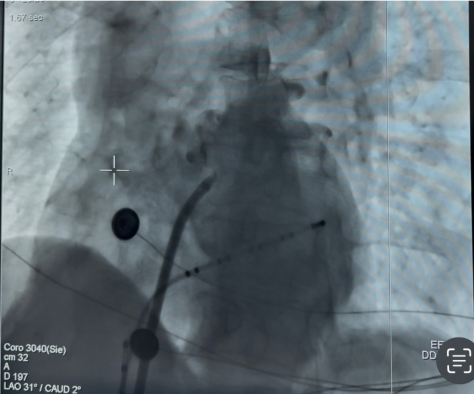

2.肺静脉造影:经导丝引导置入FARADRIVE可调弯导管鞘,对双侧肺静脉行造影明确解剖结构;

(右肺静脉造影) (左肺静脉造影)